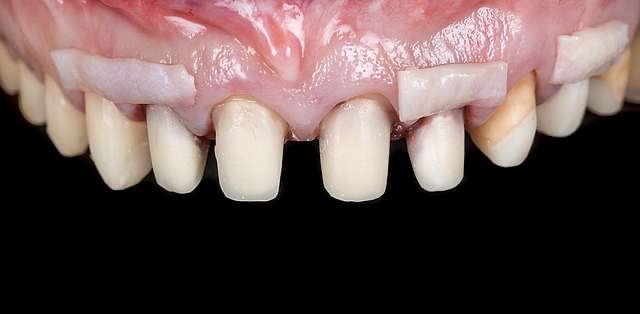

Using tissue grafts to correct tissue defects

Using tissue grafts to correct gingival levels or cover recessions